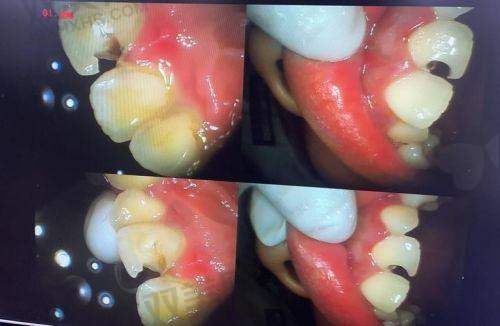

牙齿龋坏程度不同,补牙的难度和费用也不一样。如果龋洞较浅,只需要简单填充,费用相对较低。但如果龋洞较深,已经伤及牙髓,可能需要精良行根管治疗,再补牙,这样费用就会高特别多。根管治疗的费用大概在500 - 2000元每颗,再加上补牙的费用,整体花费会显著增加。所以,牙齿情况越复杂,补牙洞一般需要的钱就越多。

当龋洞较深,伤及牙髓时,通常需要多次治疗。首先要进行根管治疗,一般需要2 - 3次就诊,每次间隔1 - 2周。根管治疗完成后,还需要进行补牙或做牙冠修复,这又需要额外的时间。整个过程可能需要1 - 2个月。个体成效存在差异,具体的治疗次数和时间还会因患者的牙齿情况和修复情况而有所不同。